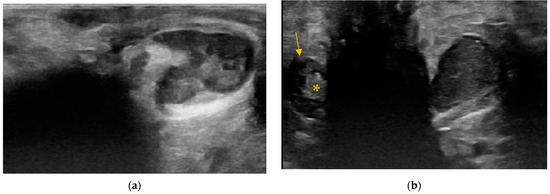

3.5. Adverse Findings

4. Discussion